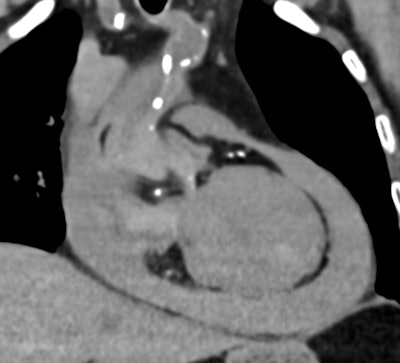

Postmortem CT reveals a large-volume hemopericardium caused by myocardial rupture, providing a definitive cause of death and avoiding the need for an invasive autopsy. All images courtesy of Drs. Susan Shelmerdine and Natasha Davendralingam.

Postmortem CT with coronary angiography and positive contrast highlights the precise location of myocardial rupture within the left ventricular wall, showcasing the value of contrast-enhanced imaging in providing accurate diagnoses without the need for autopsy.